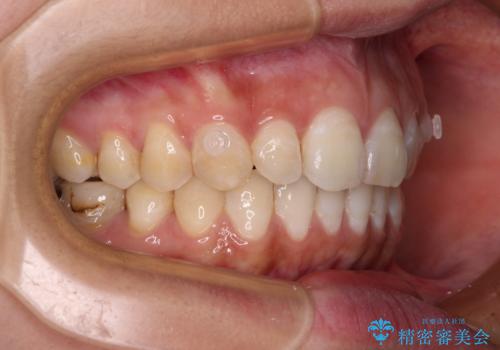

【モニター】隠れている下顎の前歯をインビザラインで改善

- 下顎の前歯が隠れていることと、デコボコを気にして来院された患者様です。

銀歯やムシ歯処置の必要な歯が奥歯にあり気になっていたので、矯正治療の途中でセラミッククラウンへ変更し、その後歯列を仕上げていくこととしました。

咬み合わせと目立っていた銀歯が改善され、患者様には大変満足していただきました。